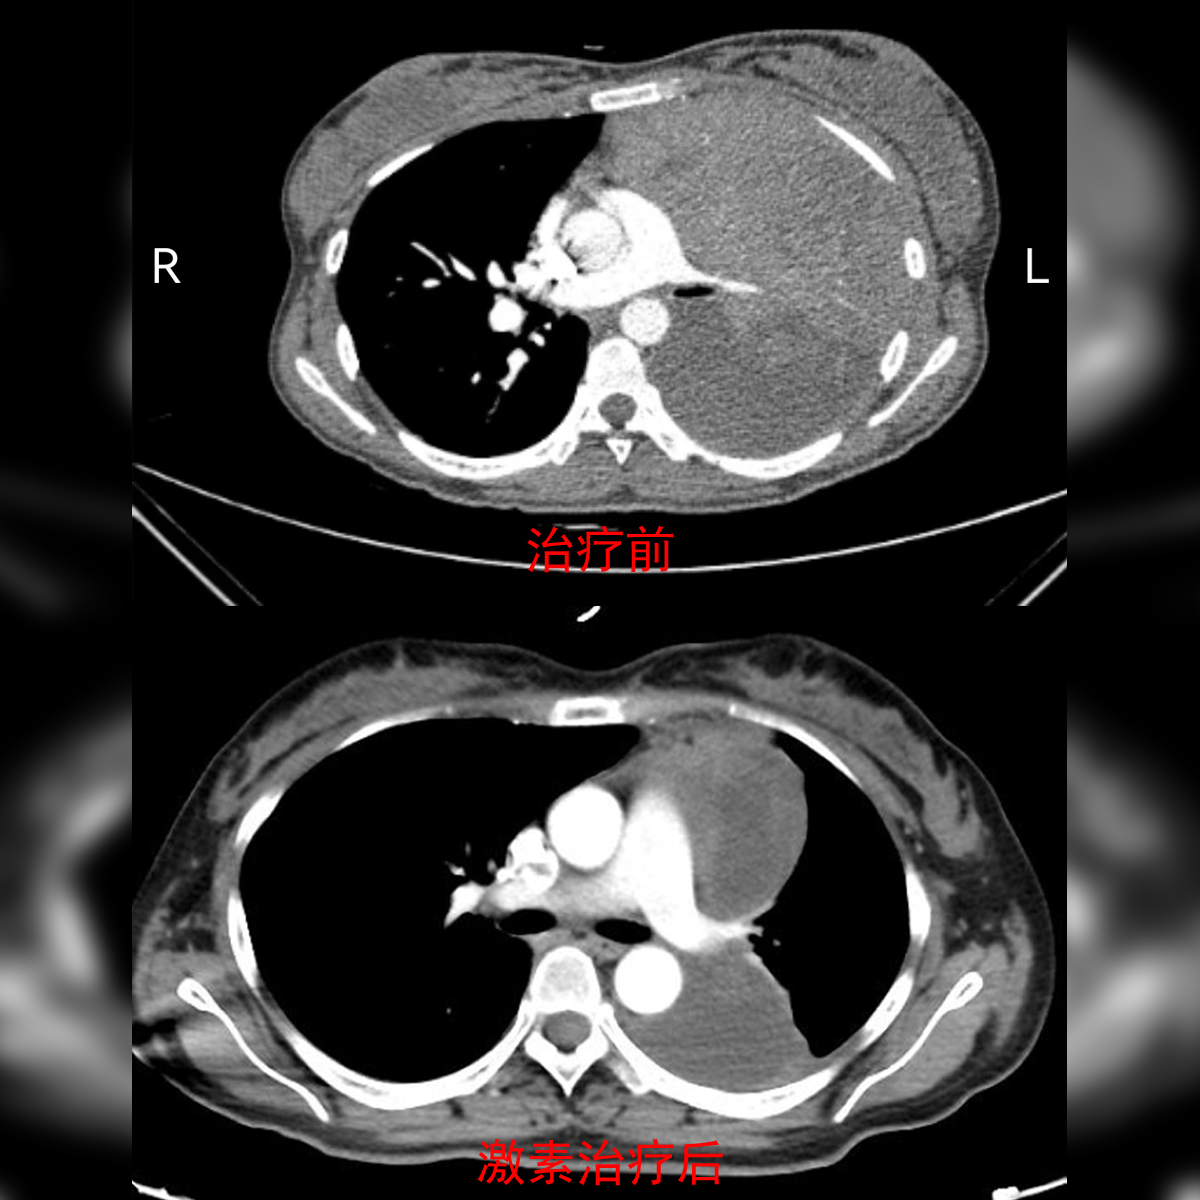

胸腺瘤是前纵隔最常见的一类肿瘤,手术切除是主要治疗方法。但是,局部进展期的胸腺肿瘤往往侵袭范围广,直接手术切除非常困难。医生们一般会先选择化疗做诱导治疗,让肿瘤“变小”,提高手术切除率。在充分评估了患者对生育的愿望、胸科医院临床研究结果及临床经验后,方主任为胡女士制定了激素治疗方案。因为,既往无论是胸科医院的临床经验,还是国外的文献报道,都有激素治疗有效促使肿瘤缩小的先例。

按照医嘱服药两个月后,胡女士的肿块明显缩小了!通过便捷的互联网医院系统,方主任明确了她的病情,告诉她“可以手术了。”那个时候,胡女士体内的肿块虽然已缩小,但仍然是个直径近20厘米的“大家伙”,且侵犯周围血管、神经和左肺,还长进了心包膜内,手术风险非常高。更让人担心的是,她的胸膜上也有一个病灶,是转移,还是肿瘤的延伸?为应对各类情况,医生们制定了充分的手术方案与应急预案,来打这场“硬仗”!